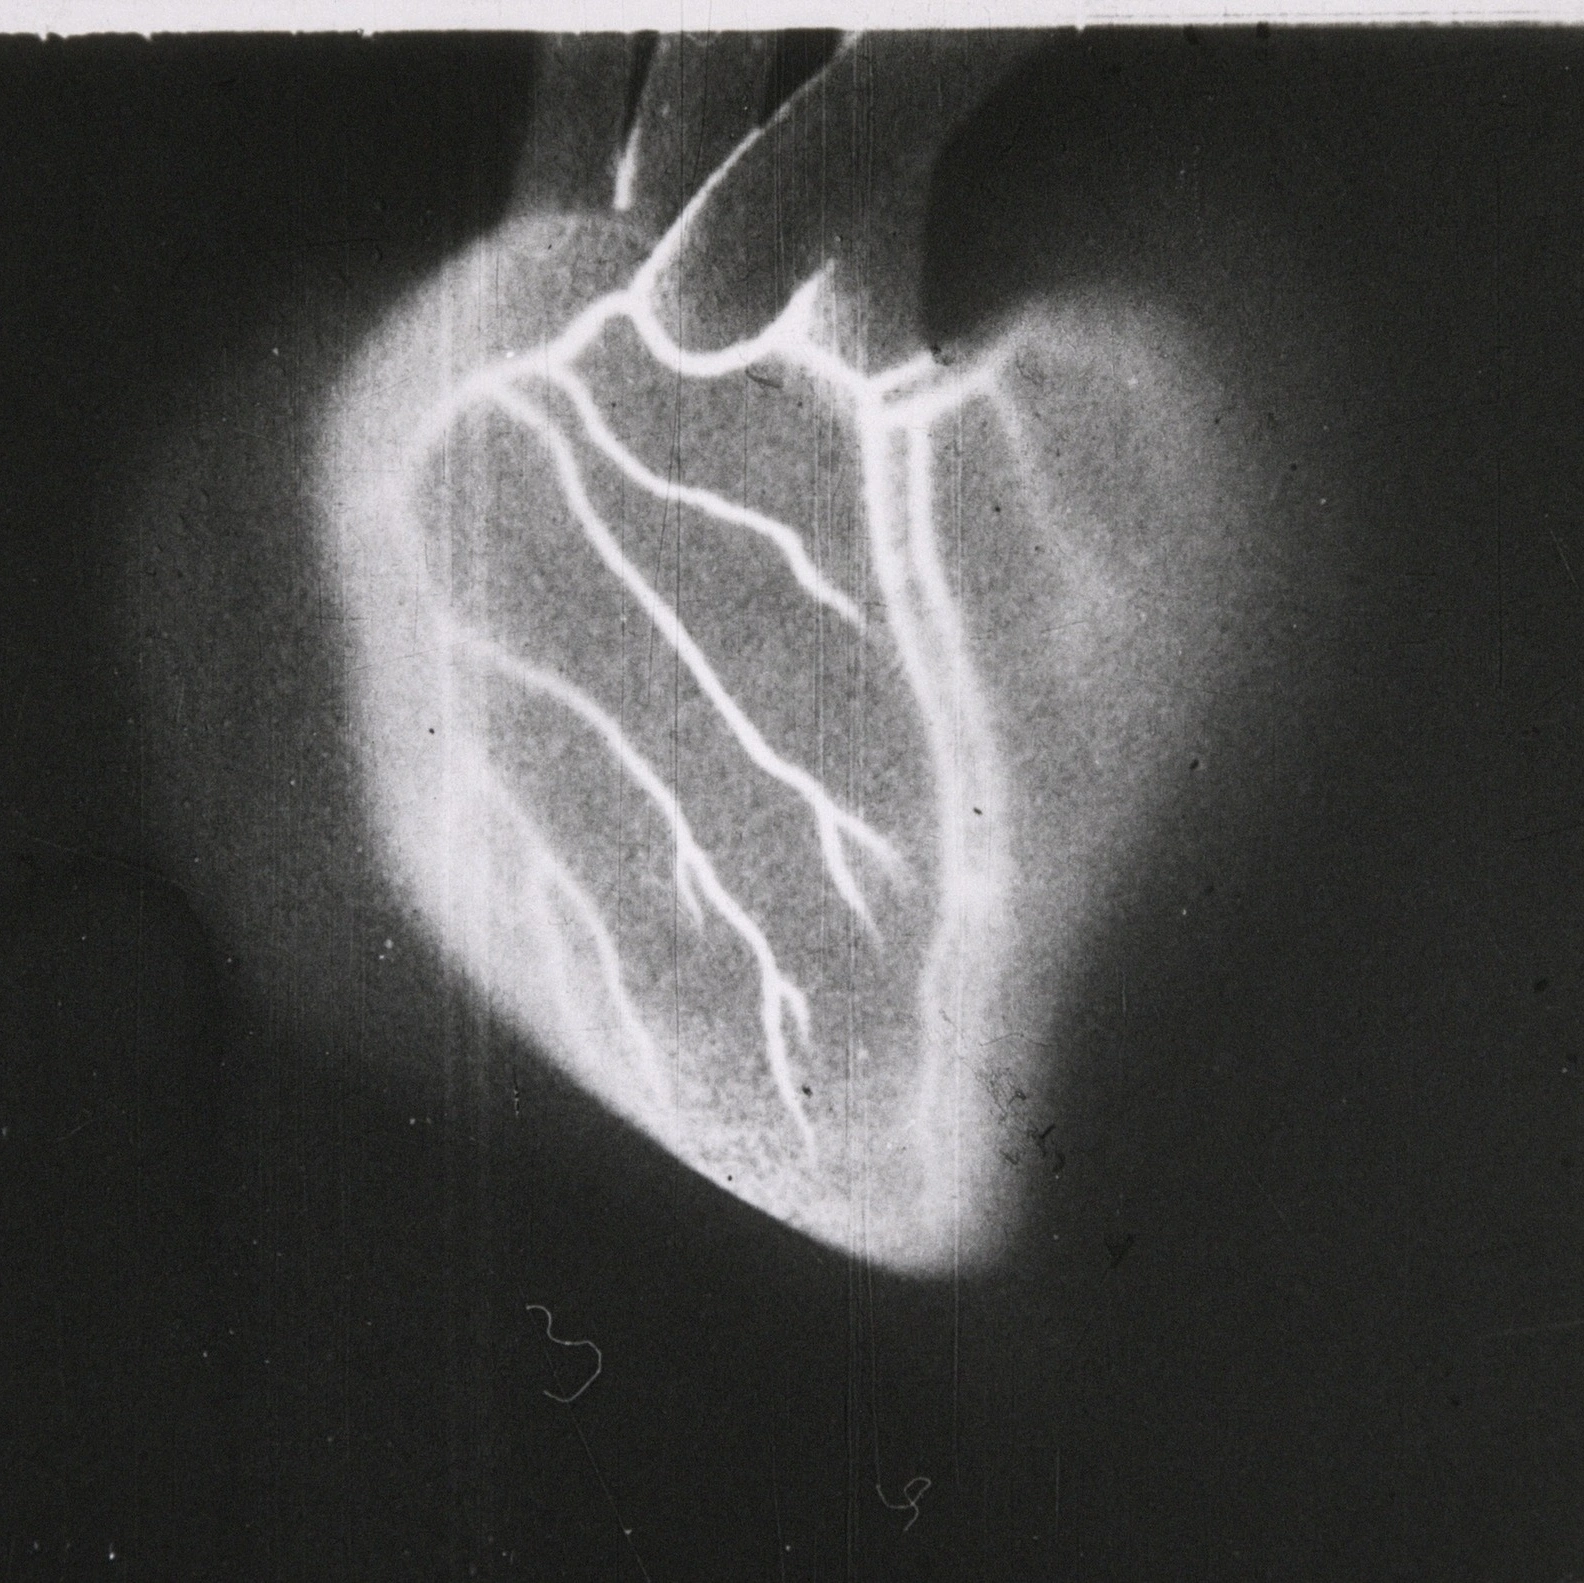

Imagine principală via Fortepan / tm. Ungaria, 1989.